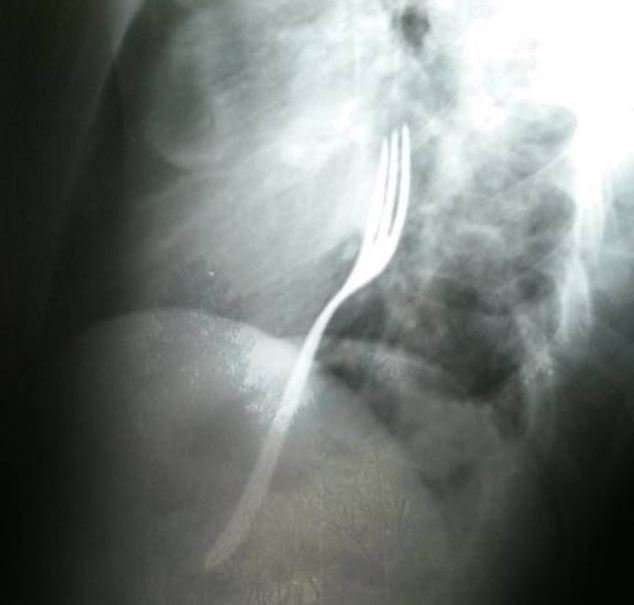

Պարզվել է, որ ռենտգենյան լուսանկարում երևացել է տղամարդու կերակրափողում գտնվող մետաղական պատառաքաղը: